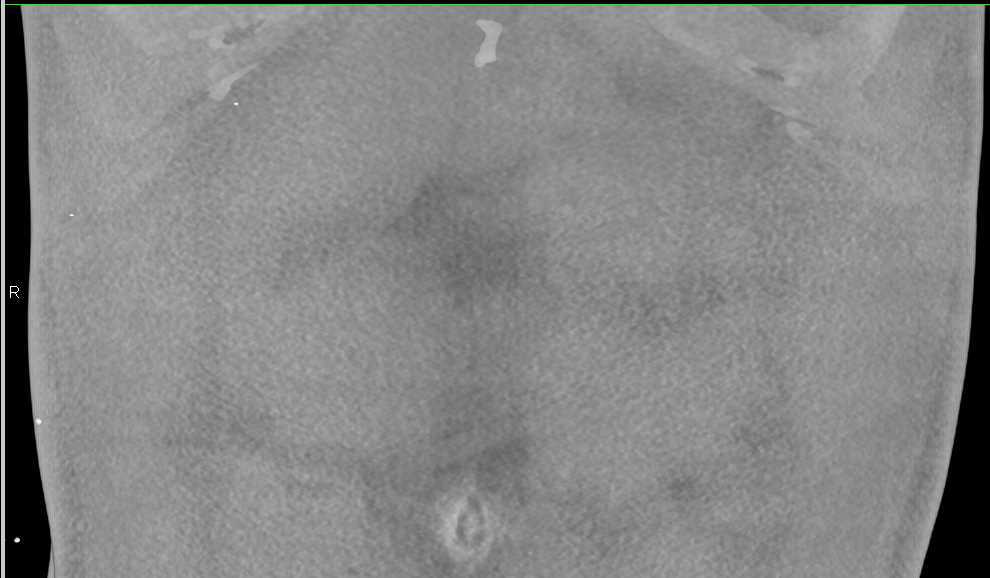

Flash Filling Hemangioma in the Right Lobe of the Liver with Adrenal Adenomas